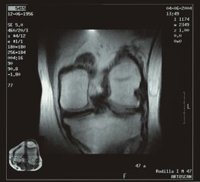

La estructura dañada en la artrosis es el cartílago, "el desgaste de ese tejido que hace de amortiguador y superficie congruente para hacer de bisagra"; por tanto, la artrosis, que afecta a cerca de siete millones de españoles, consiste en un "desgaste" del cartílago articular que puede ser progresivo.

En la artritis el tejido fundamental que se afecta es la sinovial, "una membrana que se inflama y produce liquido". La persistencia de la inflamación de la membrana sinovial condiciona que el lugar del hueso en el que se fija la membrana sinovial se dañe dando lugar a pequeñas erosiones. Además, la inflamación mantenida de una articulación hace que el cartílago, que permite el rozamiento suave entre los huesos, adelgace y desaparezca.